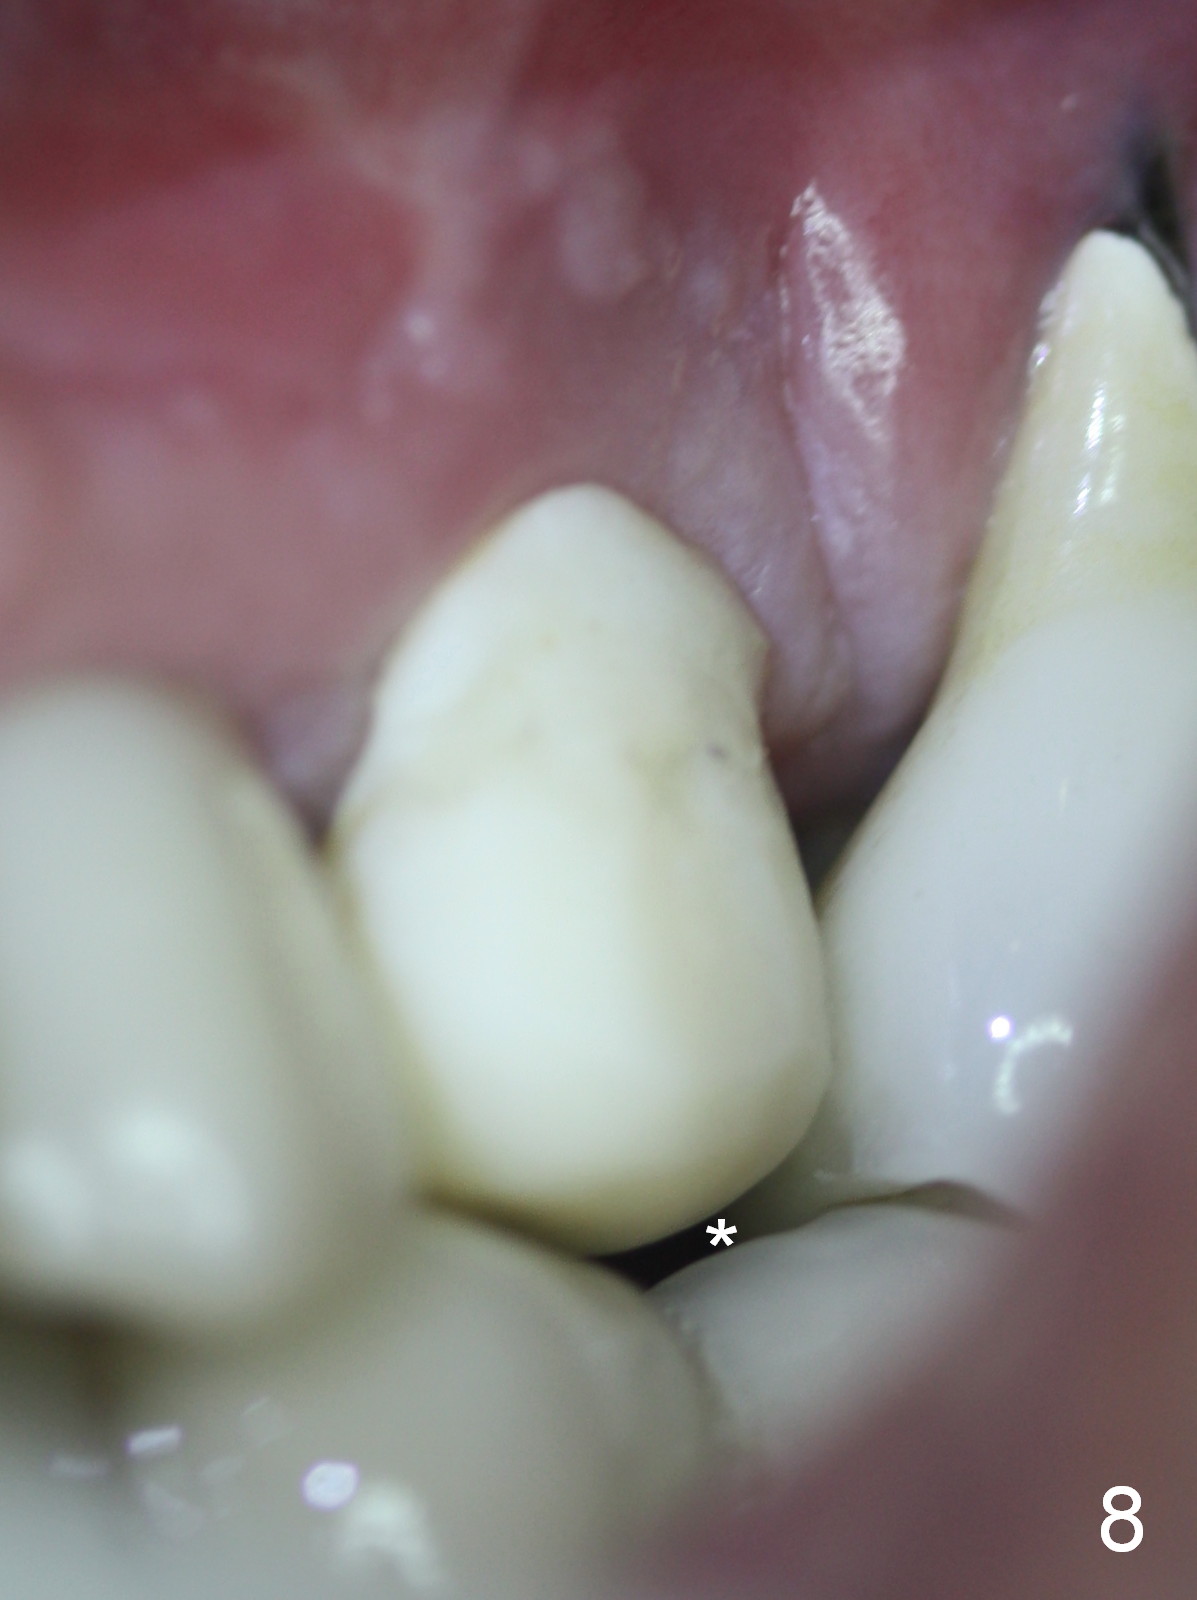

The patient returns 7 days postop, reporting that the provisional has been dislodged several times. The gingiva adapts to the provisional with occlusal clearance (Fig 8 *). The rough surface of the implant is exposed (Fig.9,10 *). It appears that some of bone graft has been lost. The provisional should be trimmed so that the gingiva may be able to grow over the rough surface.